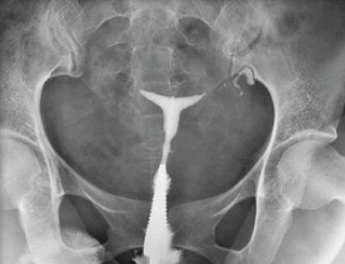

Imp: bilateral tubal block

• 자궁난관조영술에서 양쪽 난관의 완전폐쇄 소견이 보인다.

따라서 환자의 불임 원인은 양측 난관 폐쇄로 진단할 수 있다. 난관의 문제로 인해 난자가 자궁으로 내려올 수가 없기 때문에 보조생식술을 통해 임신을 시도해야 한다. 체외수정(IVF-ET)을 시도한다.

• tubal obstruction과 hydrosalpinx 소견은 자주 출제되고 있다.